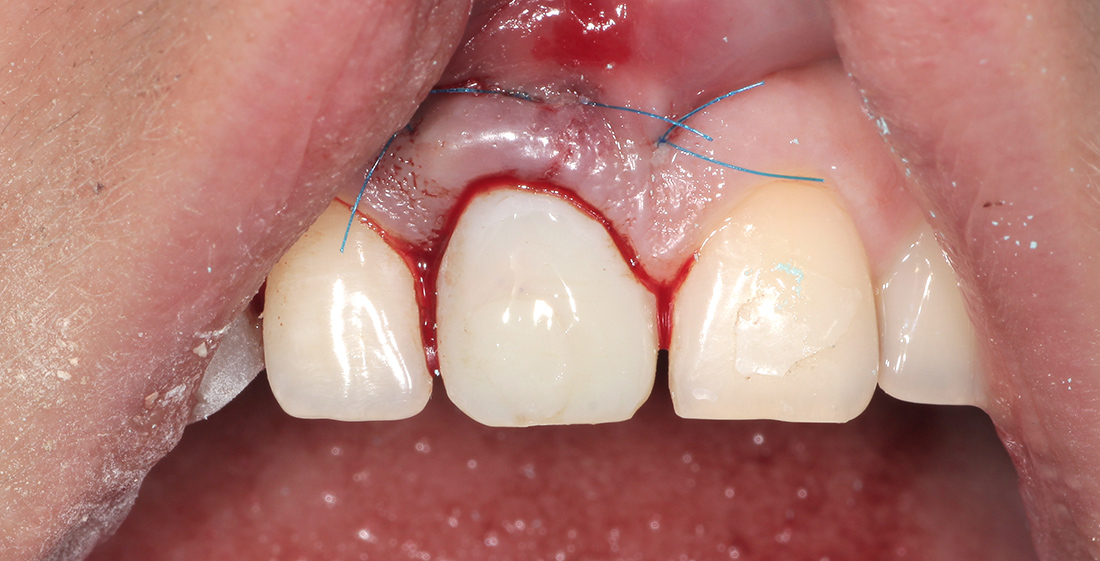

Для решения вопроса лечения было предложено два плана: классический-подразумевающий препарирование соседних зубов и изготовление мостовидного протеза; и наиболее прогрессивный- удаление зуба, непосредственная дентальная имплантация и изготовление временной коронки.

Перед нами стояла непростая задача воссоздать и даже улучшить исходную ситуацию, т.к. в условиях высокой линии улыбки и значительной потери мягких и твердых тканей, окончательная реставрация должны была быть максимально эстетичной.

Под местной анестезией был удален зуб, установлен имплант, проведена пластика мягких тканей и фиксирована временная коронка. Через три месяца проведена оценка импланта, и мы перешли к замене временной коронки на постоянную. Опорой для коронки на импланте послужил индивидуальный циркониевый абатмен.